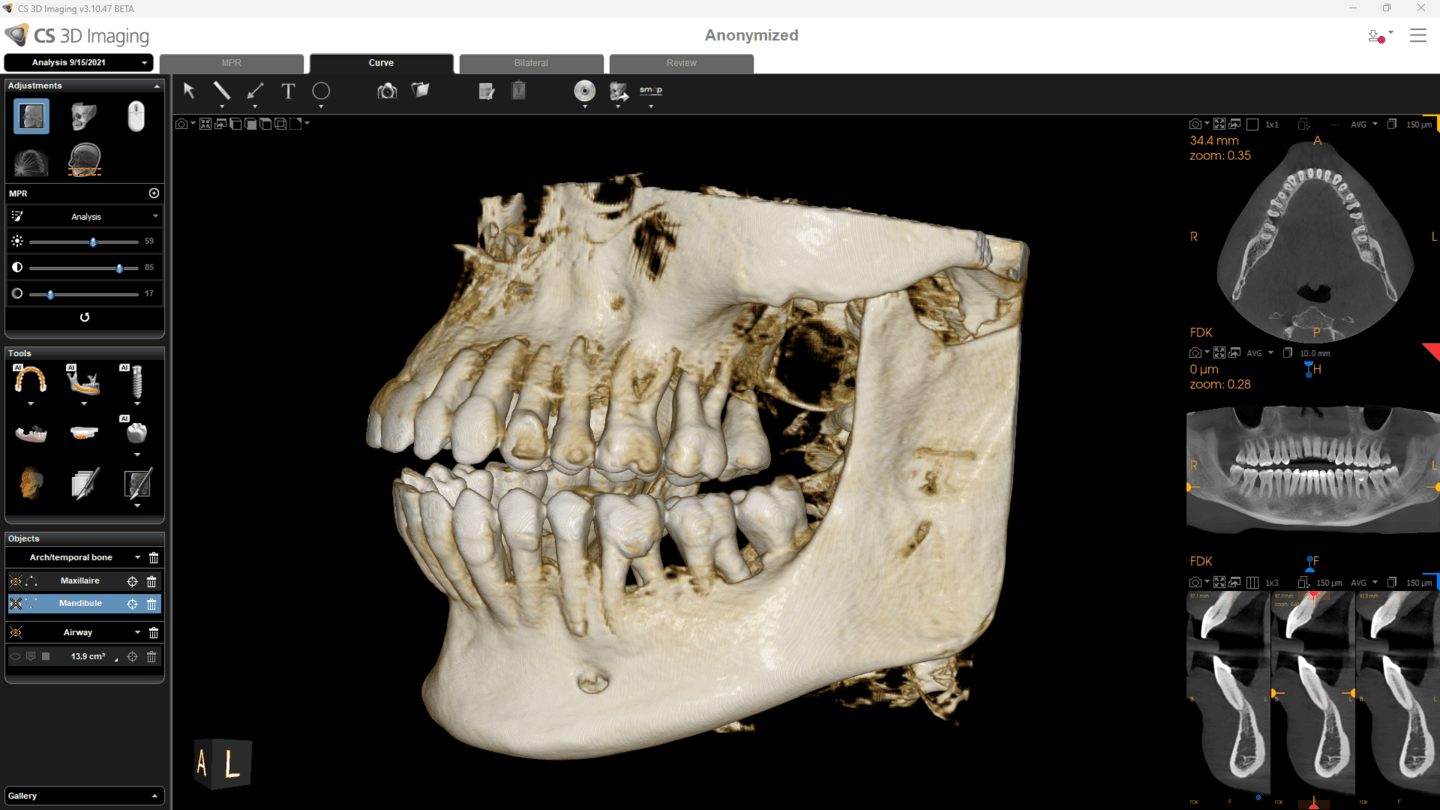

Fra 4×4 cm til et komplet 16×17 cm volumen. CS 9600 dækker endodonti, implantatplanlægning, oral kirurgi, ortodonti, ENT og maksilofacial kirurgi — alt fra én og samme platform.

Kliniske anvendelser

CS 9600 dækker et bredt spektrum af kliniske indikationer med dedikerede optagelsestilstande.

| AI-funktioner | Nervekanal, PDIP implantatplanlægning, AI Insights |